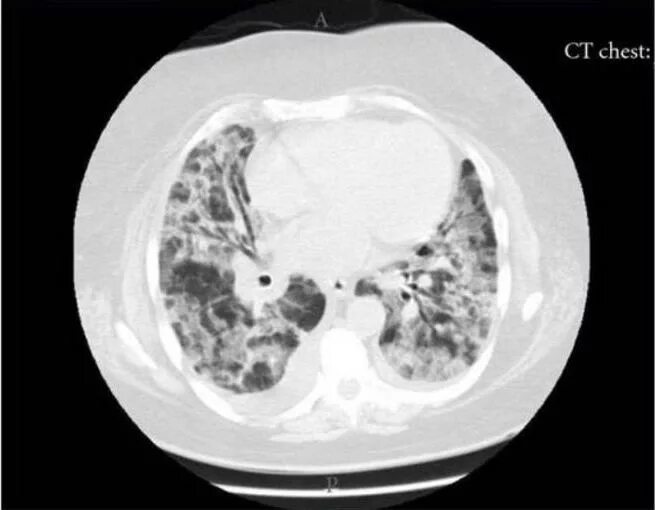

Фиброз кт